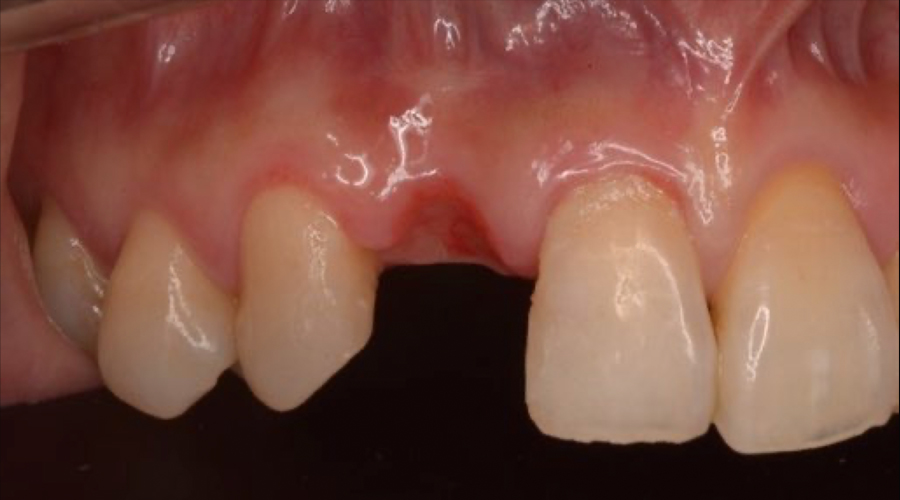

- 治療内容

- 欠損部位に対して、人工歯根を埋入し上部構造として補綴物をかぶせる治療です。

- 治療に伴うリスク

- 治療後の口腔管理が不適切な場合、埋入したインプラント周囲に感染・炎症を起こし、脱落する可能性がございます。